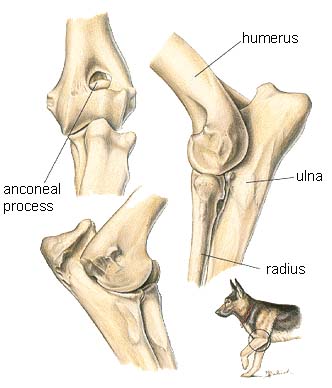

The musculoskeletal system includes all the muscles, bones and joints.

- Elbow

Elbow